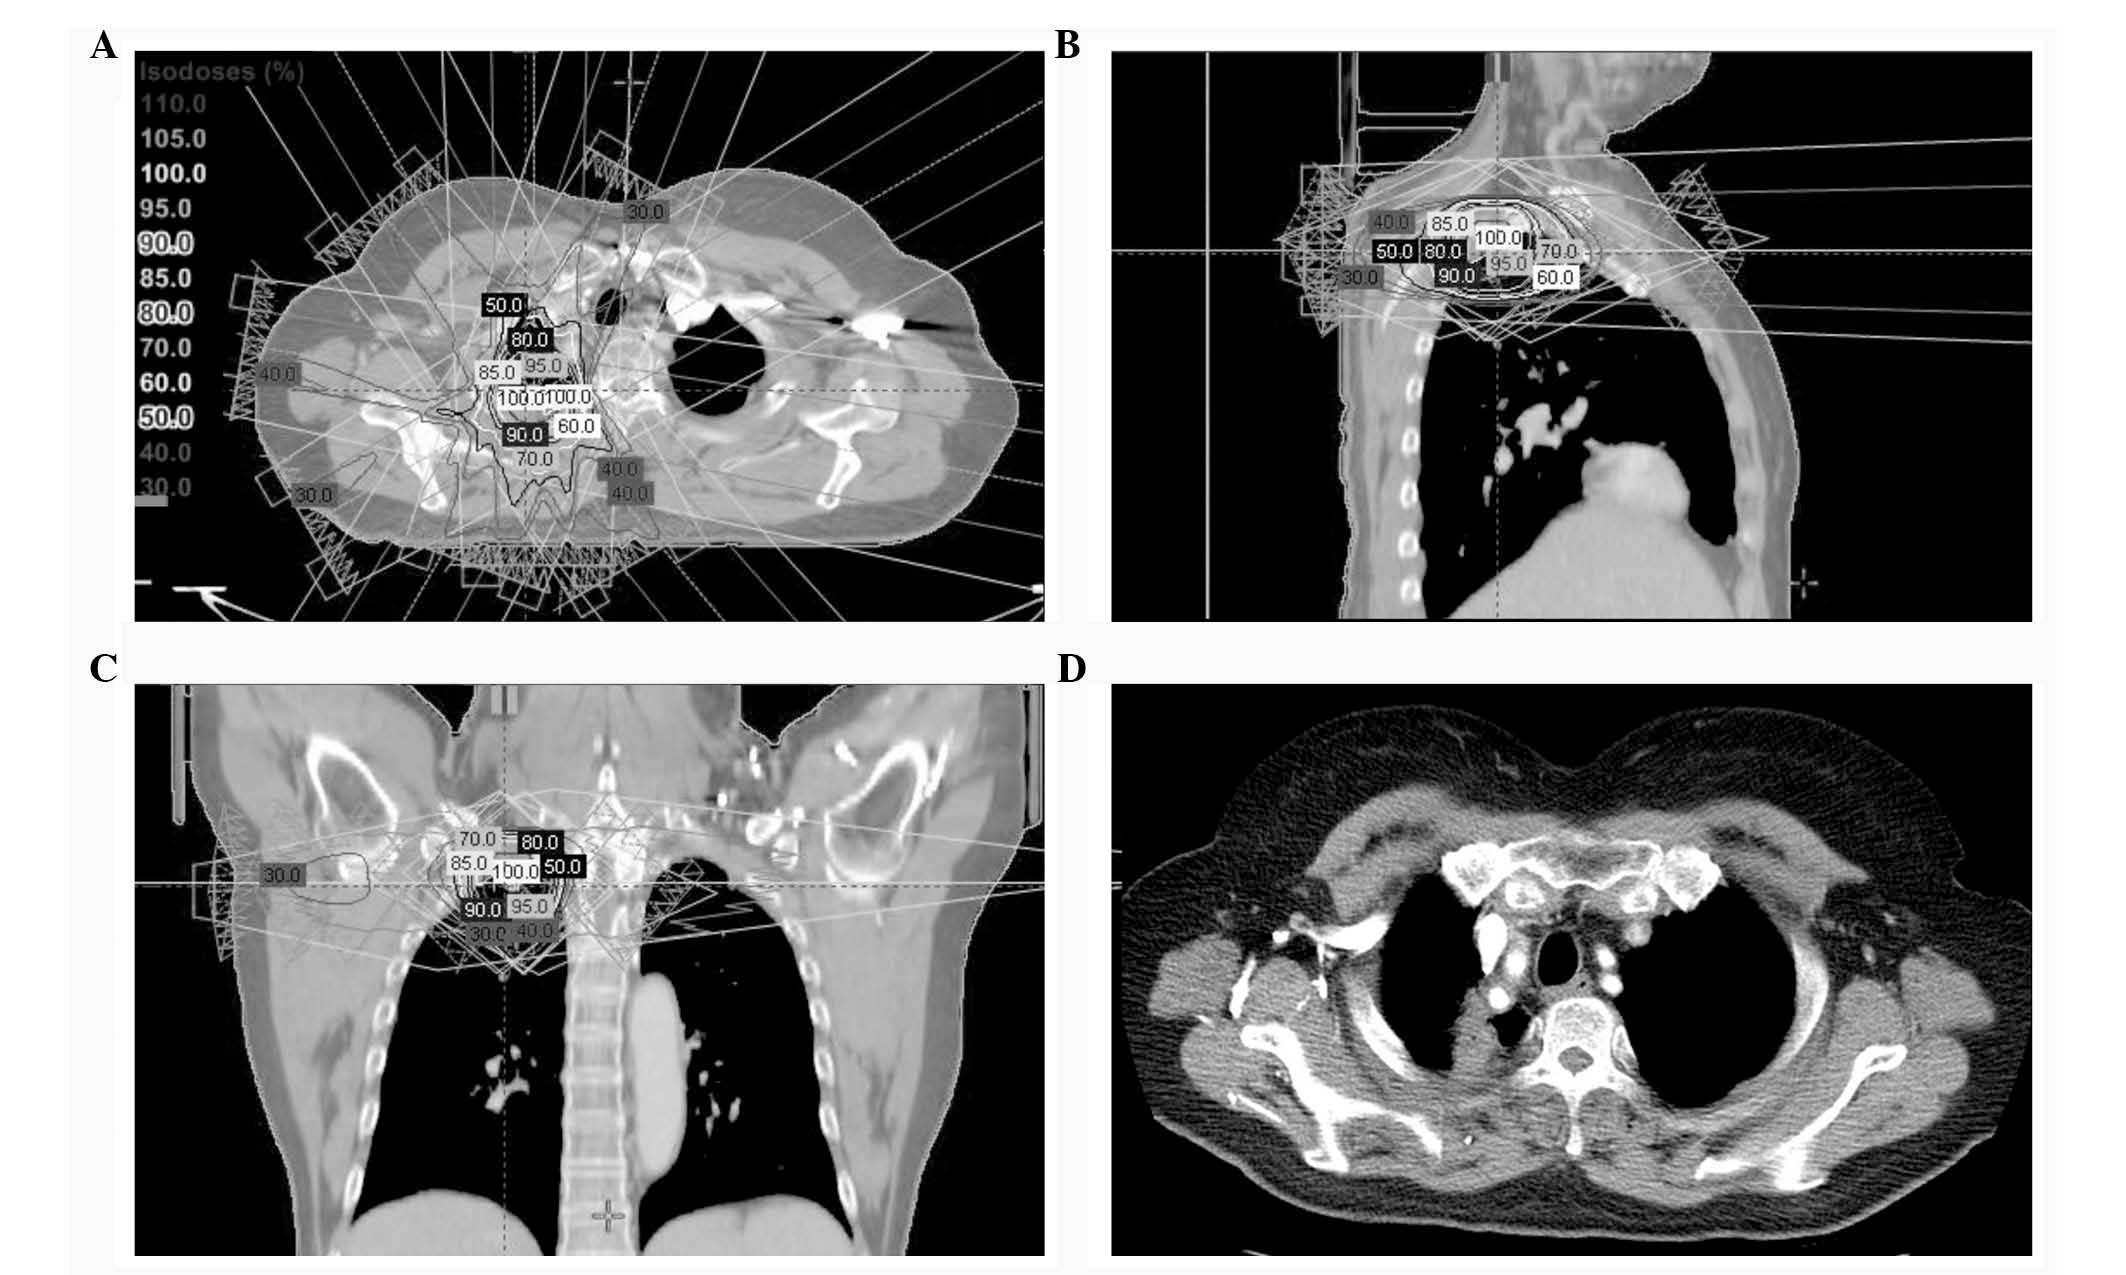

SBRT was performed in August 2011 using a Novalis Tx system (Varian Medical Systems, Palo Alto, CA, USA; Brainlab, Feldkirchen, Germany). During the simulation process, the patient was immobilized in the supine position with her arms above her head. The simulation was conducted using 4-dimensional CT (Brilliance CT Big Bore; Philips Medical Systems, Cleveland, OH, USA) and a real-time position-management system (Varian Medical Systems). The gross tumor volume was delineated on each respiratory phase CT image using the ‘lung window’ setting. The clinical target volume was equivalent to the gross tumor volume. The internal target volume was created from the sum of the clinical target volumes during the 10 respiratory phases. The planning target volume was generated by adding a 0.5-cm isotropic set-up margin around the internal target volume. Adjacent organs at risk were outlined, including the lungs, spinal cord, esophagus, trachea, proximal bronchial tree, heart, great vessels, ribs, and skin. The SBRT plan was created using the Eclipse treatment planning system (Varian Medical Systems) and 6 MV photons, with inhomogeneity corrections. The fixed-field intensity modulated RT used 7 non-opposing coplanar beams (Fig. 1A–C). The dose fractionation scheme was 48 Gy in 4 fractions delivered on consecutive days, and the prescribed dose covered 95% of the planning target volume conformally. Prior to each treatment, cone beam CT was performed to minimize the set-up error. Prophylactic cranial irradiation (PCI) (8) was given in September 2011, as 25 Gy in 10 fractions using 6 MV photons and two opposed lateral fields.

Figure 1.

(A-C) Intensity-modulated SBRT plan using 7 non-opposing coplanar beams. The dose distribution with isodose lines ≥30% of the prescription dose is also shown. (D) Chest CT 40 months after SBRT shows focal non-enhanced consolidation in the right upper lobe, without 18F-fluorodeoxyglucose uptake on the positron emission tomography-CT (not shown), indicating radiation-induced fibrosis. SBRT, stereotactic body radiation therapy; CT, computed tomography.

The patient was followed-up every 3 months for the first 2 years and every 6 months thereafter. A physical examination and chest CT were performed at each visit and PET-CT yearly. A complete response to SBRT was observed along with signs of radiation pneumonitis or fibrosis on follow-up imaging (Fig. 1D), although the patient developed no pulmonary symptoms. The patient is alive with no evidence of disease 4 years after treatment. The present study was performed in accordance with the guidelines of the Institutional Review Board and informed consent was obtained from the patient prior to commencing SBRT.